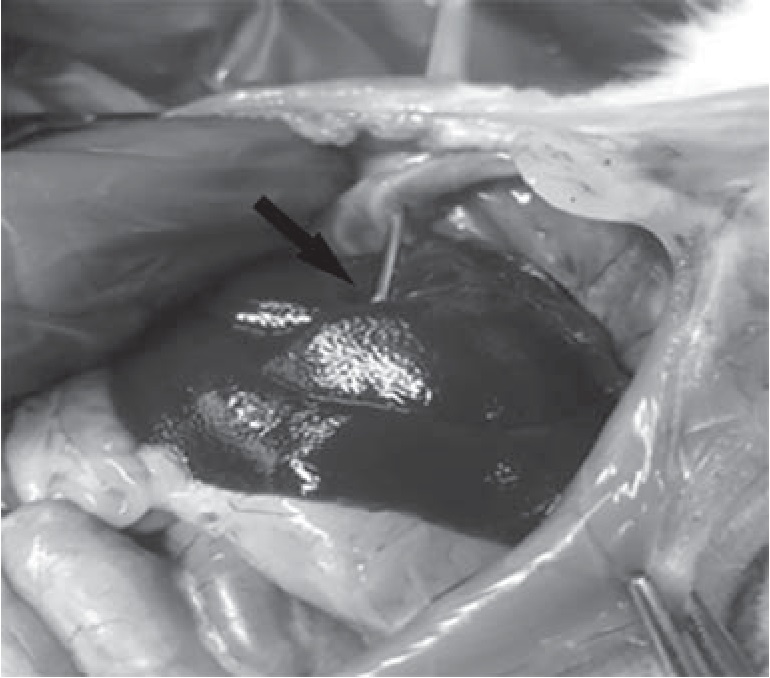

Крысам 2-й группы биопсия выполнялась также через межреберный доступ при этом исключался разрез кожи, так как в системе предусмотрен встроенный троакар в просвет коаксиальной иглы. В точке Р осуществлялся прокол под прямым вертикальным углом до ощущения провала в брюшную полость (рис. 8).

Рис. 8. Техника прокола коаксиальной иглой с троакаром

Далее осуществлялся прокол капсулы печени на глубину приблизительно 0,2 см. Заметим, что погружать иглу более 0,4 см нецелесообразно по причине того, что во время нажатия на спусковой механизм АС происходит выдвижение троакара из просвета коаксиальной иглы на 1 см, тем самым появляется риск прокола печени насквозь с последующим повреждением нижележащих органов. После чего необходимо взвести спусковой механизм АС и нажатием на рычаг вырезать биоптат печени. Полученный биоптат помещался в пробирку с формалином (рис. 9). Профилактика кровотечений выполнялась по ранее описанной методике.